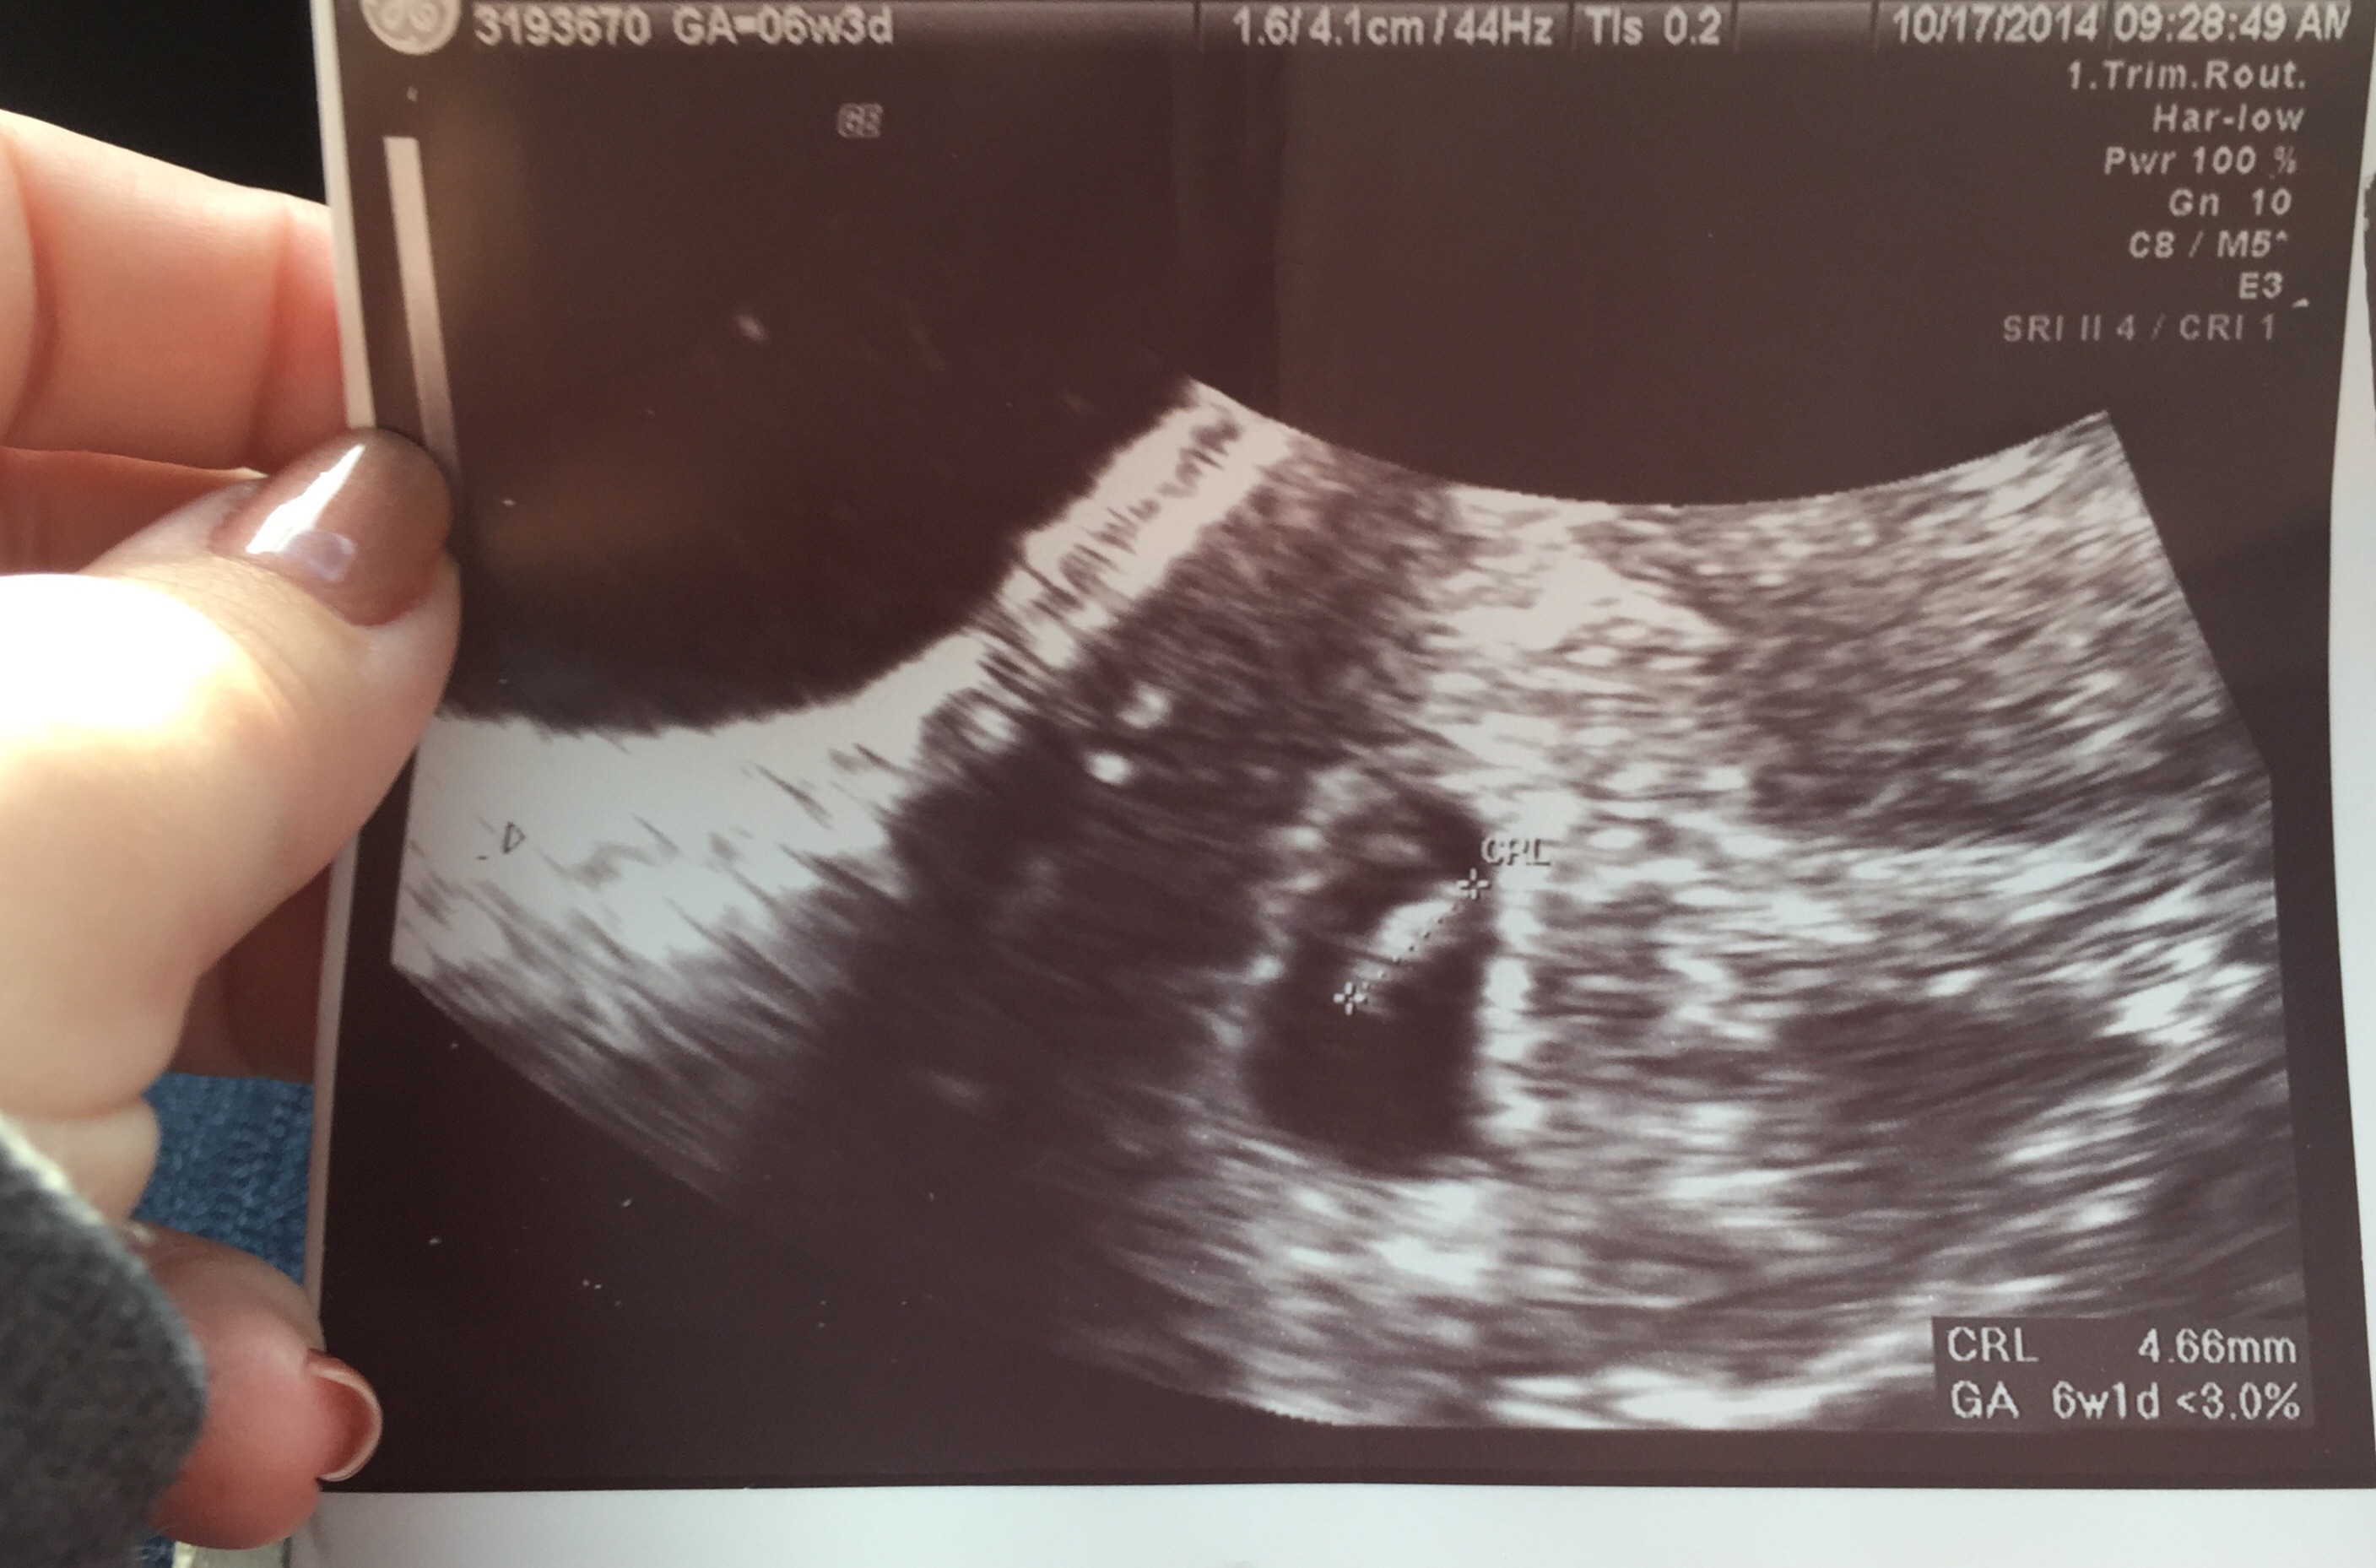

• My OB tracked me at 6w1d today. Here is today's US and the next one is at 16 weeks

• Here's mine I thought I was 7 weeks but I was 6 weeks 5 days